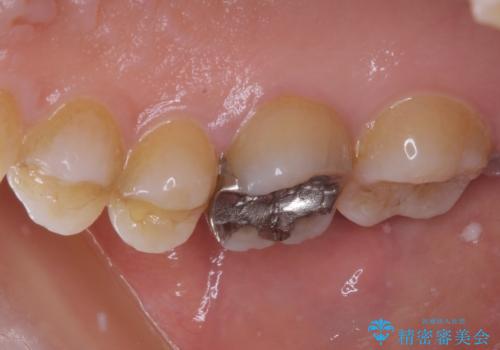

- 近医にて抜歯が必要と診断されたとのことで来院された患者様です。

術前の診査では、歯が破折している可能性が高いものの、確実に抜歯が必要と診断ができない状態でした。

状況次第では抜歯が必要となり、その際にはインプラント治療を行うことを了承いただいた上で、破折していない場合には根管治療を行うこととしました。

土台の材料を外して顕微鏡下で確認したところ、歯根にまで及ぶ破折が認められたため、インプラント治療を行うこととしました。